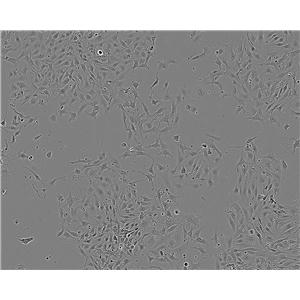

S91小鼠黑色素瘤细胞系是一种常用的实验动物模型,用于研究黑色素瘤的发生、发展和治疗。该细胞系来源于C57BL/6小鼠,具有高度的恶性程度和侵袭性,能够快速生长并形成肿瘤。

高度恶性:S91小鼠黑色素瘤细胞系具有高度的恶性程度,能够在体外快速生长并形成肿瘤。

侵袭性:S91小鼠黑色素瘤细胞系具有较强的侵袭性,能够穿过基底膜并进入周围组织。

易转移:S91小鼠黑色素瘤细胞系容易发生转移,可以通过血液或淋巴系统扩散到其他部位。

可重复性好:S91小鼠黑色素瘤细胞系的生长和转移过程可以重复多次,且结果稳定可靠。

S91小鼠黑色素瘤细胞系广泛应用于肿瘤学研究中,包括肿瘤发生机制的研究、抗肿瘤药物的筛选和评价、肿瘤免疫治疗的研究等。